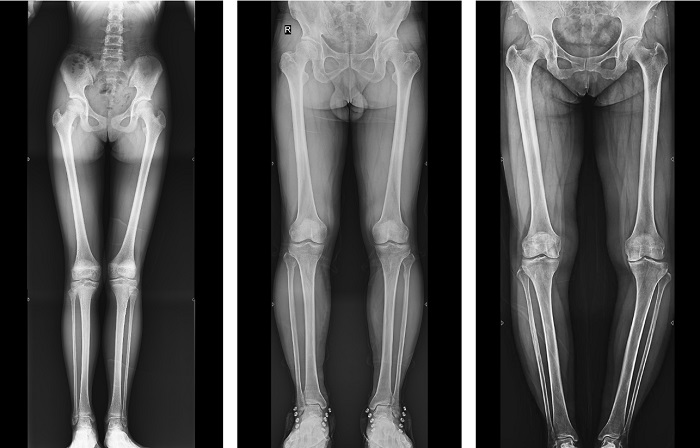

動態DR全景拼接功能突破平板尺寸長度限制,可進行立臥位攝影,對脊柱、下肢及下肢靜脈造影進行分段攝片,然后對分段圖像進行拼接,在一幅X光圖像上完整顯示全脊柱或下肢整體形態,獲得全脊柱或全下肢圖像,有效解決了傳統X光片不能一次成像問題,通過直觀顯示脊柱和下肢的整體解剖形態及側凸部位,為臨床治療提供重要參考依據。

▲全下肢DR影像

普利德多功能動態DR進行全脊柱全下肢圖像拼接時,影像密度均勻、清晰、接緣處過渡自然,圖像質量高,完全能滿足臨床觀察、診斷及測量要求。拍片過程也更加方便快捷,使患者得到快速診斷,及時治療,為臨床醫生和患者帶來更大的便利,大大助力醫院醫療服務能力的提升!